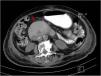

Upper endoscopy revealed a Forrest IIB duodenal ulcer (Fig. 1), which due to the complexity associated with its anatomic location, was treated only with removal of the attached clot and endoscopic adrenaline injection. Erosive gastritis and Los Angeles grade C esophagitis were also identified. Twenty-four hours later, the patient developed acute oral feeding intolerance, with a tendency toward low blood pressure. She showed neurologic signs of lethargy and presented with skin and mucous membrane dehydration, associated with a serum sodium level of 149mmol/l, oliguria with creatinine of 1.2mg/ dl, and BUN of 38mg/dl. She also presented with abdominal distension, epigastric pain, and multiple episodes of nausea and vomiting. Given that her hemoglobin level did not drop, and her clinical status did not worsen, suspected rebleeding was ruled out.